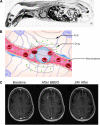

A long-standing goal of translational neuroscience is the ability to noninvasively deliver therapeutic agents to specific brain regions with high spatiotemporal resolution. Focused ultrasound (FUS) is an emerging technology that can noninvasively deliver energy up the order of 1 kW/cm2 with millimeter and millisecond resolution to any point in the human brain with Food and Drug Administration-approved hardware. Although FUS is clinically utilized primarily for focal ablation in conditions such as essential tremor, recent breakthroughs have enabled the use of FUS for drug delivery at lower intensities (i.e., tens of watts per square centimeter) without ablation of the tissue. In this review, we present strategies for image-guided FUS-mediated pharmacologic neurointerventions. First, we discuss blood-brain barrier opening to deliver therapeutic agents of a variety of sizes to the central nervous system. We then describe the use of ultrasound-sensitive nanoparticles to noninvasively deliver small molecules to millimeter-sized structures including superficial cortical regions and deep gray matter regions within the brain without the need for blood-brain barrier opening. We also consider the safety and potential complications of these techniques, with attention to temporal acuity. Finally, we close with a discussion of different methods for mapping the ultrasound field within the brain and describe future avenues of research in ultrasound-targeted drug therapies.